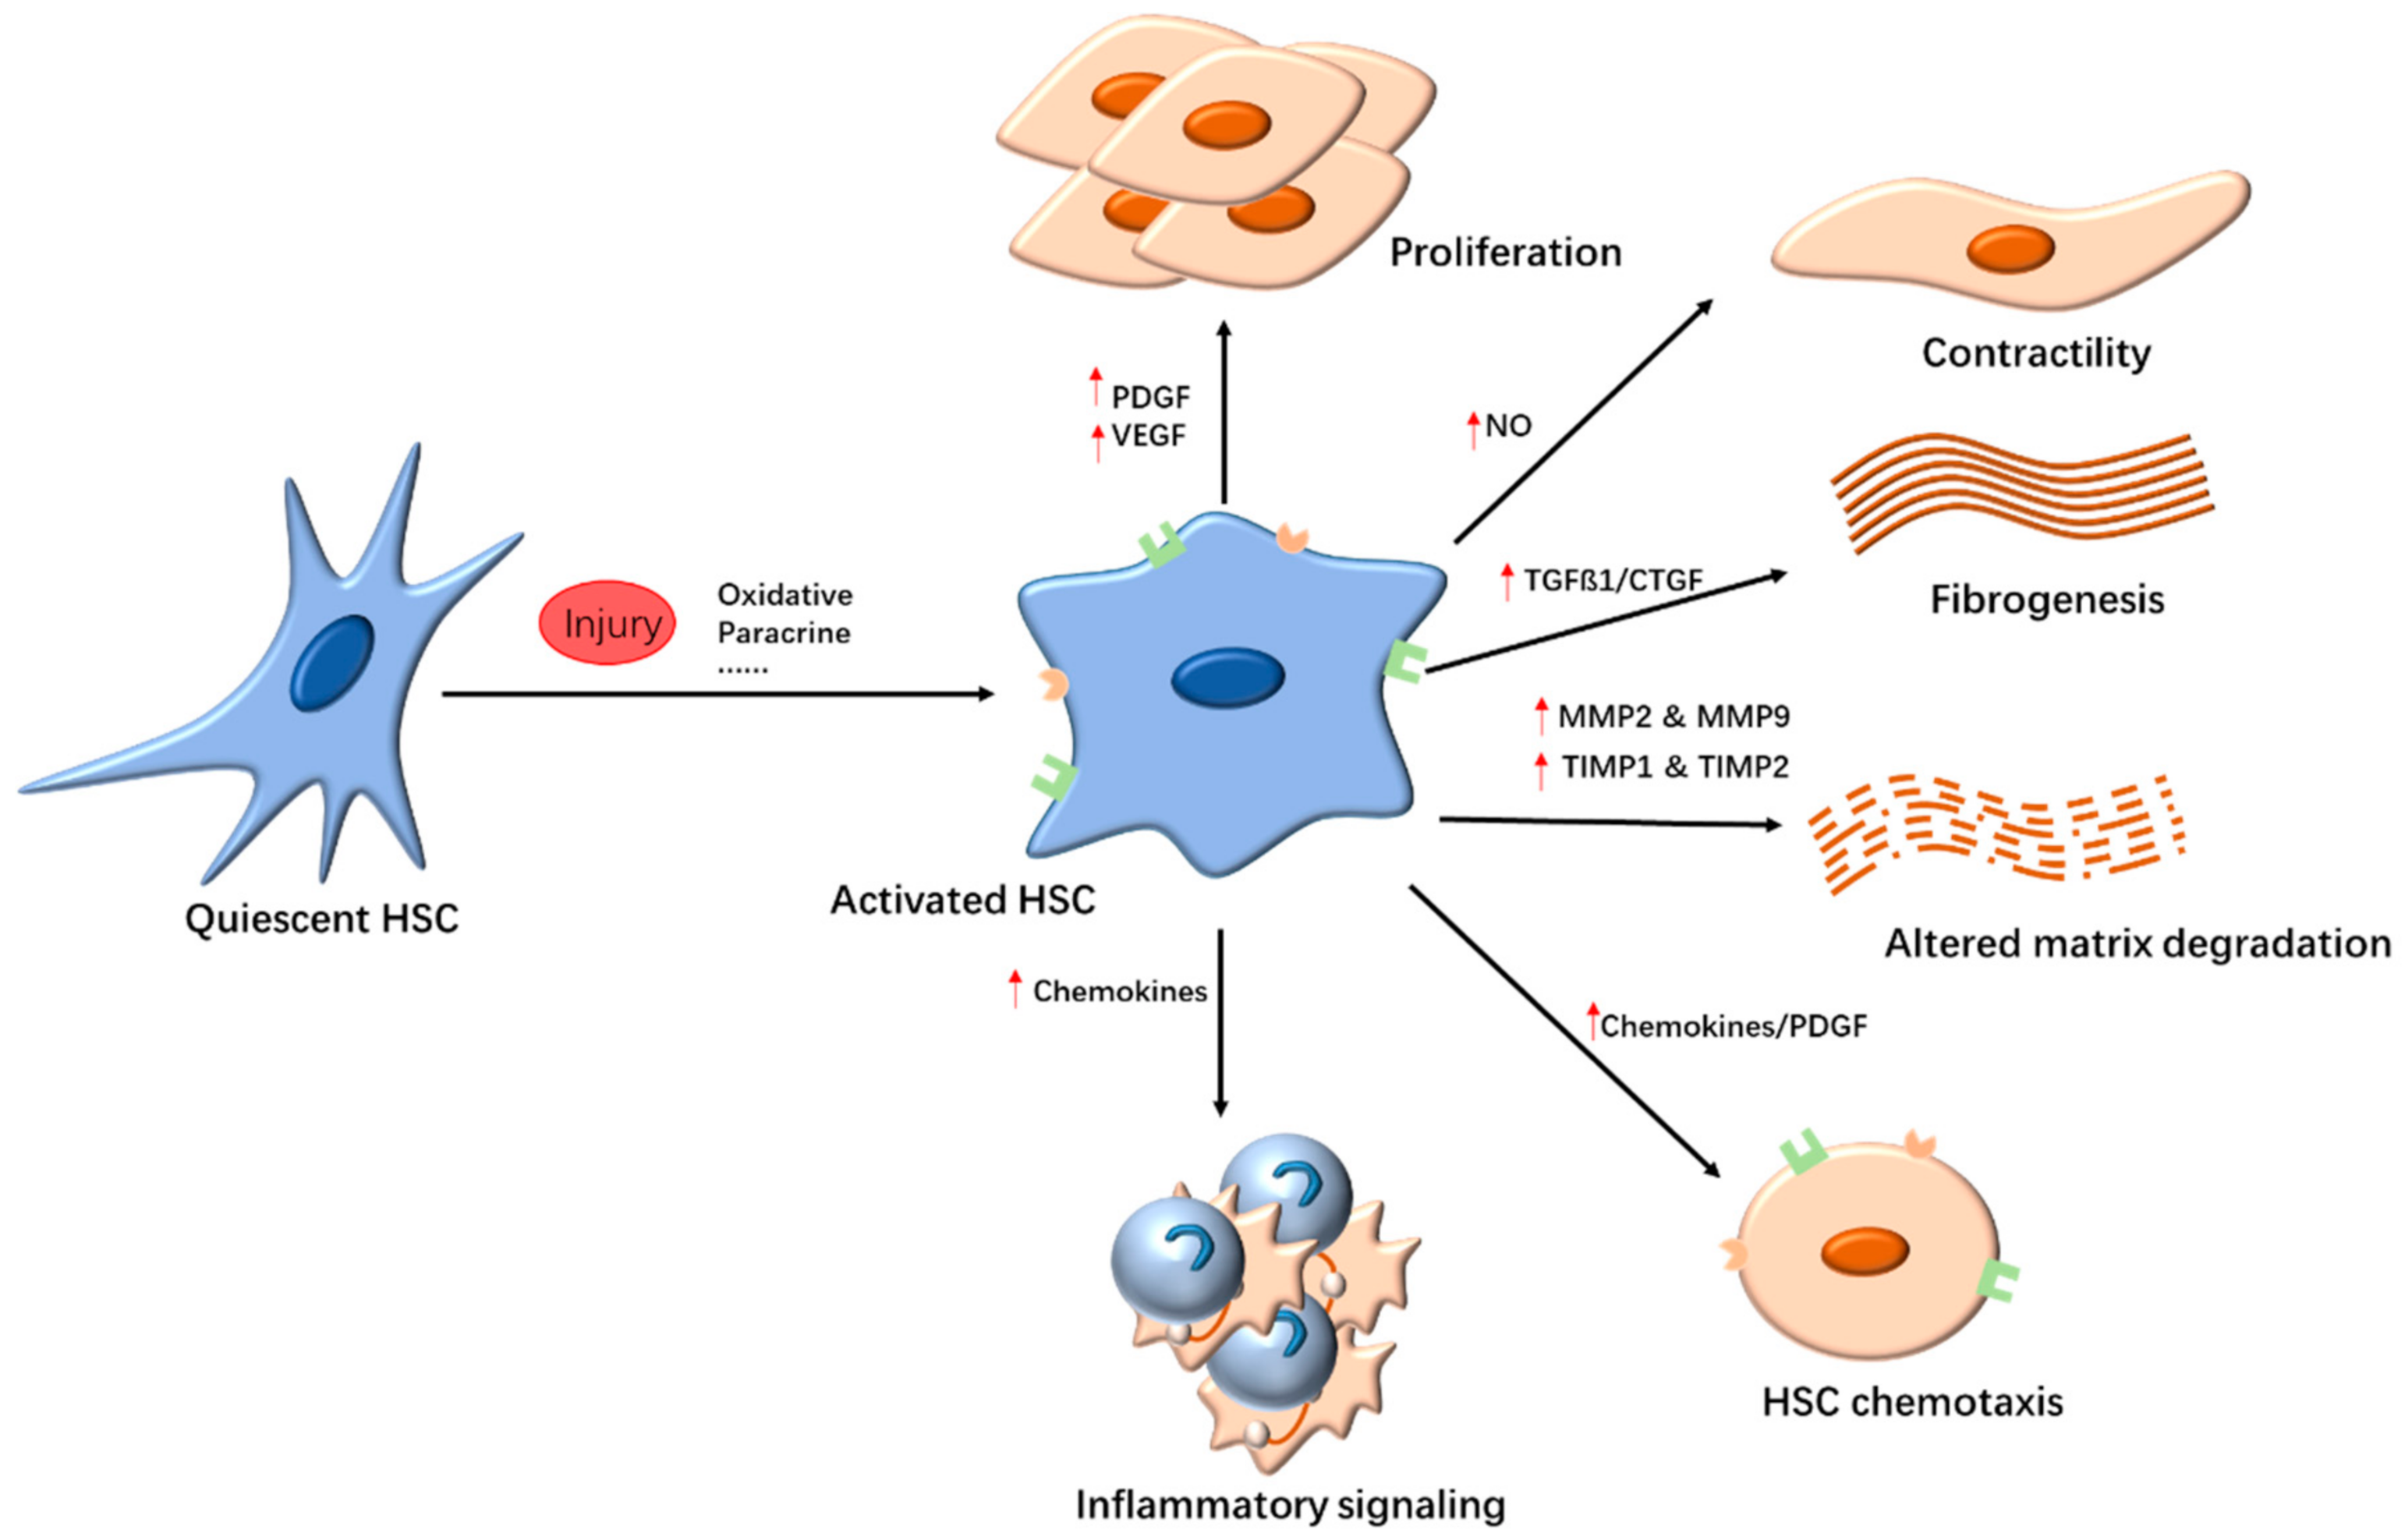

2.1. Targeting HSCs